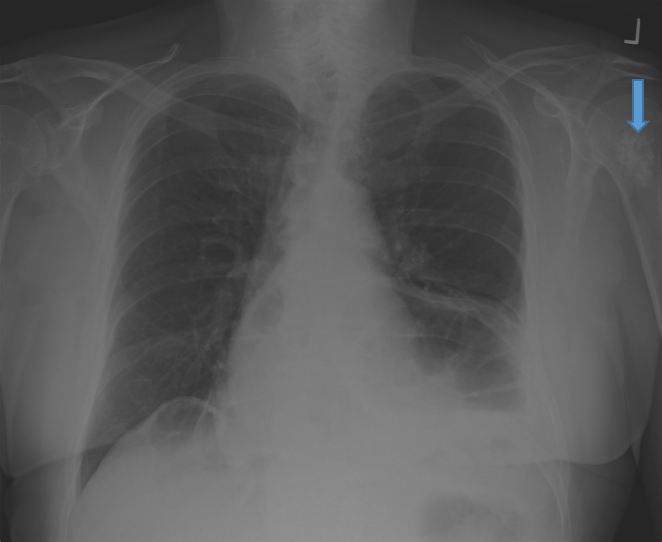

Chest x-ray in an older man confirmed a diagnosis of pneumonia but revealed an asymptomatic lesion in the left humerus. What is in the differential?

A 68-year-old man with no significant medical history had a flu-like illness for three weeks including a cough that produced purulent sputum. He had no fever, chills, chest pain, or ear pain, but felt lethargic. In spite of this, he went to work every day. Three months earlier, he received Prevnar 13 vaccine IM in the left deltoid, and a pertussis booster vaccine (Tdap) SC, but did not receive vaccination against influenza. Because the productive cough continued, bringing up copious frothy secretions, he went to an urgent care facility for evaluation. On examination, his vital signs were: temperature, 37 oC, blood pressure, 112/80 mm Hg, pulse, 80 beats/min, respiratory rate, 20 breaths/min. On auscultation, bibasilar wheezing was noted (L > R). Initial peak flow measured 350 L/min, which improved to 370 L/min after a respiratory treatment. No labs or cultures were taken. Posterioranterior (Figure 1) and lateral radiographs revealed left middle lobe opacification, confirming a diagnosis of pneumonia. The patient received azithromycin orally for 5 days and an albuterol inhaler and improved.

In addition to pneumonia, the final radiologic report mentioned “lytic lesions in the proximal left humerus” (Figure 1, arrow) and recommended follow up with an orthopedic specialist. The patient had no history of cancer, no bone pain, or limitation of range of motion of the left arm.

Figure 1. Posterioanterior chest radiograph showing left middle lobe opacification and lytic lesion (arrow) in the left proximal humerus.